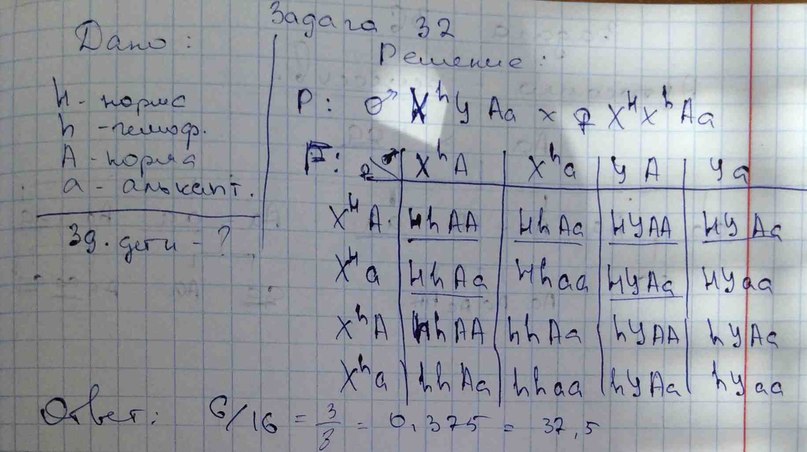

Генетика гемофилии: рецессивные гены и их проявления